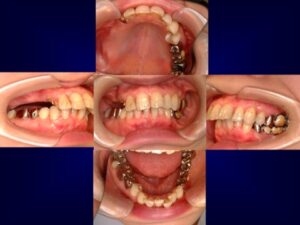

ケース2:上下に多くの問題があった70代後半男性

この方は虫歯や歯周病で残存歯が少なく、グラグラの歯が多い状態でした。最初は保険のクラスプ義歯を入れていたものの安定せず、硬いものを噛めないため外していることが多かったそうです。外見を重視してナイロン義歯を試されましたが、期待したような咬合回復は得られず、全体の再治療を希望して来院されました。

まず全顎の虫歯と歯周病の治療を行い、上顎は残存歯すべてに内冠をかぶせて連結し、全体を支えるテレスコープ義歯を製作しました。装着後は「入れ歯」というよりは取り外し可能な長いブリッジの感覚で、違和感がほとんどないとのことです。

このケースは「残った歯をチーム化して守る」発想が有効であった例です。